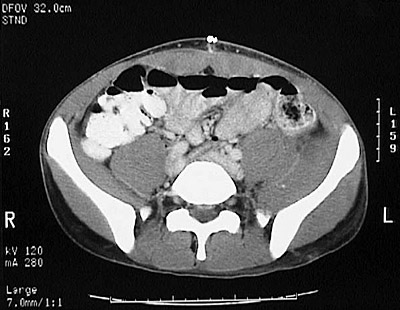

[L5] This is a normal pelvic CT scan with contrast demonstrating the colon and rectus abdominis muscle and psoas muscle and iliacus muscle and external and internal oblique muscles and multifidus muscle and gluteus medius muscle and right common iliac artery and right common iliac vein and left common iliac artery and left common iliac vein and right iliac wing and left iliac wing in the pelvis.